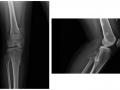

Figura 1- Radiografia de tórax e abdômen, evidenciando cateter umbilical venoso com extremidade visível à esquerda dos corpos vertebrais torácicos em topografia do átrio esquerdo( seta).

Figura 2 - A radiografia em perfil evidencia a extremidade do cateter direcionado posteriormente em topografia do átrio esquerdo(seta).

Cateter umbilical venoso mal locado, com extremidade no átrio esquerdo (Figuras 1 e 2) com reposicionamento adequado (Figuras 3 e 4).

Dentre as principais complicações associadas ao uso do cateter umbilical venoso, destaca-se a localização intra-cardíaca, o que pode levar à perfuração atrial, ao tamponamento cardíaco e à arritmias. Algumas vezes, a extremidade do cateter pode passar para o átrio esquerdo através do forâmen oval, ainda patente nesta fase da vida do RN. Nesta situação, as radiografias evidenciam a ponta do cateter em topografia anatômica do átrio esquerdo( Figuras 1 e 2 ).